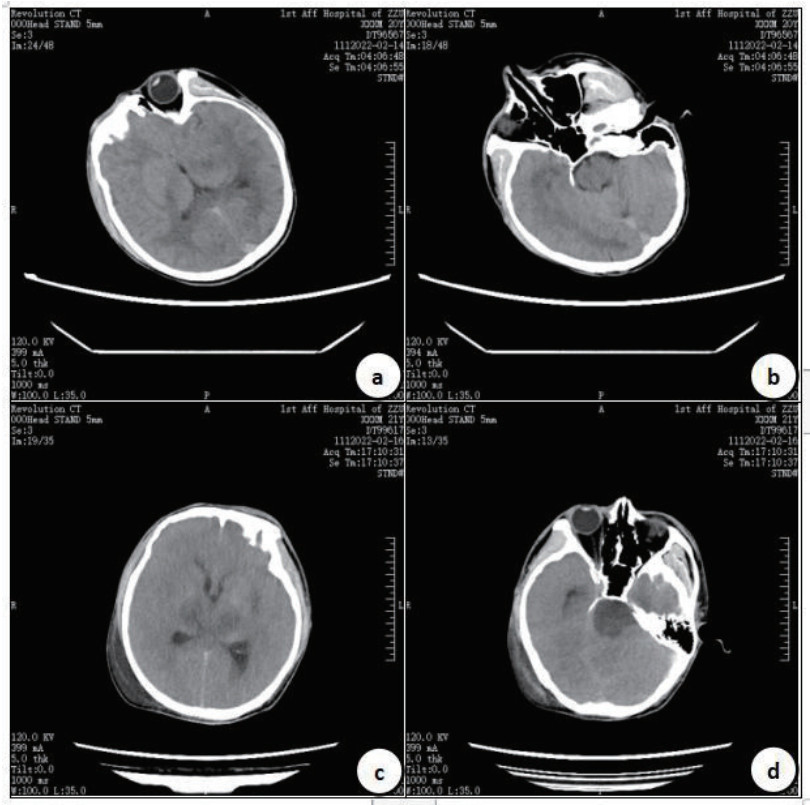

2 典型病例病例1:患者男,21岁,以“口服敌草快100 mL 5 h”代主诉入院,既往体健。体格检查:体温37.5℃,脉搏130次/min,呼吸30次/min,血压120/82 mmHg(1 mmHg=0.133 kPa),烦躁,对答不切题,定向障碍,查体不配合,心肺听诊未见明显异常,病理征阴性。实验室检查:血常规:白细胞(WBC)24.16×109/L、红细胞(RBC)5.06×1012/L、血小板(PLT)231×109/L,中性粒细胞百分比(N%) 91.6%。肝功能:谷草转氨酶(AST)43 U/L,谷丙转氨酶(ALT)25 U/L。肾功能:肌酐(Cr)105 μmol/L,肾小球滤过率63.965 mL/min/1.73 m2。动脉血气分析:pH 7.482,动脉血氧分压(PO2)89.4 mmHg,二氧化碳分压(PCO2)30.50 mmHg,实际碳酸氢根(HCO3-)22.80 mmol/L,乳酸1.6 mmol/L。入院查头颅CT未见明显异常(见图 1)。距服药时间36出现氧和不能维持,行气管插管接呼吸机辅助通气,46 h出现抽搐、全身强直性阵挛发作,查体见双侧瞳孔散大固定,牙关紧闭,全身肌张力增强、角弓反张,给予地西泮、苯巴比妥抗癫痫药物应用后癫痫样发作症状可被控制,但出现血压下降至60~80/30~40 mmHg,给予补液、升压药物应用。61 h后行头颅CT检查示:丘脑、脑干密度减低。脑干梗死,脑弥漫性肿胀。自动离院后死亡。

| 入院时头颅CT(a、b),入院61 h后头颅CT(c、d)示:脑实质灰白质分界不清,脑沟、脑裂变浅,部分脑池变窄,枕大池显示不清,丘脑、脑干密度减低,小脑扁桃体似向下移位,小脑幕及大脑镰密度稍增高,中线结构居中。 图 1 病例1的CT结果 Fig 1 CT results of Case 1 |

在病例1中,笔者观察到患者在服药36 h后出现头痛、呕吐加剧,随后出现全身性强直性阵挛发作,双侧瞳孔均散大,对光反应消失。头颅CT检查提示小脑扁桃体疝形成,考虑脑水肿形成脑疝压迫延髓,发生呼吸、循环衰竭。这可能是因为DQ中毒后引起的血管源性水肿和细胞毒性水肿同时存在,导致严重脑水肿,甚至脑疝形成[5]。然而并不是所有出现DQ相关中毒性脑病患者均出现脑水肿表现,可能与人群中脑血流异质性较大和免疫系统炎症反应不同有关,具体机制尚不清楚。文献复习中,笔者发现DQ相关中毒性脑病尸检结果多表现出弥漫性脑水肿、基底节区血管周围出血灶[15],大脑切面多以局限于脑桥的异常为主[13]。这与本研究观察到的临床表现和影像学结果相一致。